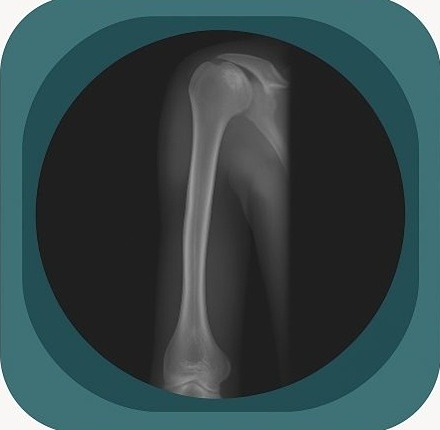

Explore high-quality X-ray anatomy from head to toe. Our database features carefully labelled images to visualize fine structuresโ€”perfect for radiologists, students, and surgeons.